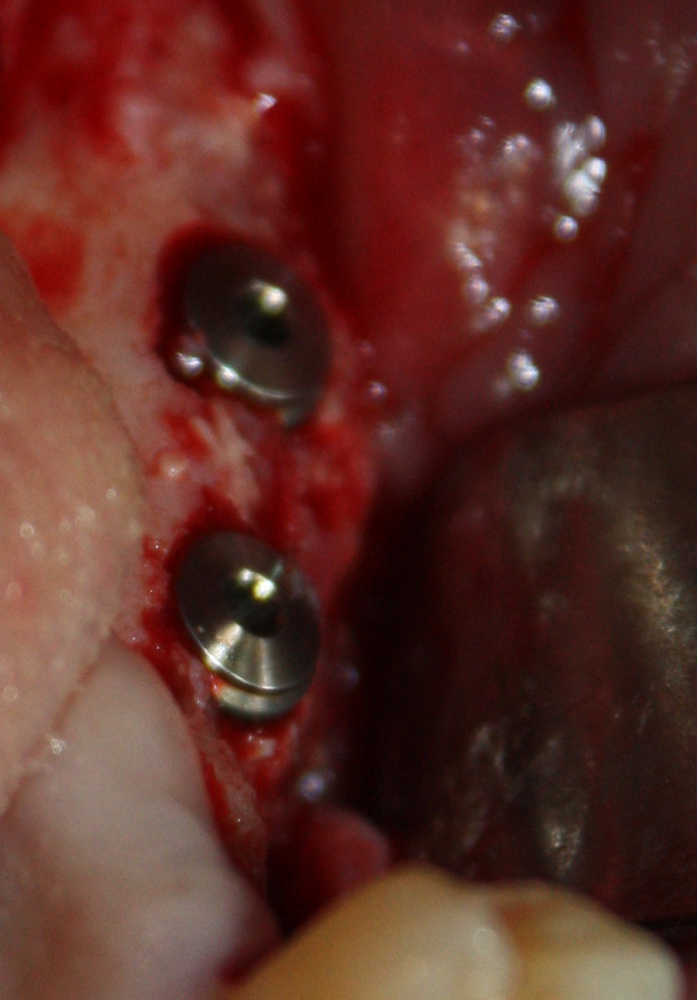

Например, в следующей ситуации:

Оставить так, как есть — это значит, сильно рисковать имплантом и объемом альвеолярного гребня — фактически, большая часть импланта пятого зуба «висит в воздухе». Поэтому получившуюся костную полость мы заполняем аутокостной стружкой в смеси с Bioss и закрываем коллагеновой мембраной BioGide:

При необходимости, мембрану можно фиксировать пинами.

Через три месяца результат:

можно ставить формирователи и заканчивать лечение:

В указанном выше случае использование костных блоков просто невозможно.